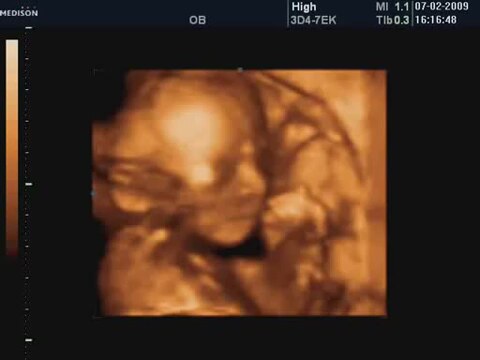

22 Haftalık Bebeğin 4 Boyutlu Ultrasın Görüntüsü